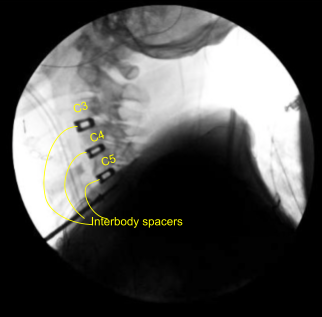

Case Study: Anterior discectomy and fusion C3-4, C4-5 and C5-6 and Insertion of interbody titanium cage globus; C3-4, C4-5 and C5-6

Bilateral foraminotomies were done using Kerrison punch 3.0. All the discs were thoroughly decorticated to achieve fusion. Once adequate foraminotomy and discectomy was done, a spacer was inserted to size the disc. After sizing, 8-mm Globus titanium cage filled with titanium interbody spacer, filled with autologous bone graft, mixed with Trinity and DBX was inserted finding it in adequate position.

Attention was moved to the C4-5 disc space. Caspar pin was inserted into the C5 body and expansion of C4-5 done with a self-retaining retractor. Skyline was moved inferiorly to retract medially and laterally. Discectomy was done in a similar fashion followed by excision of the posterior longitudinal ligament and bilateral foraminotomies. After adequate excision the sizing was done, Globus titanium spacer filled with Trinity and autologous bone graft and DBX was inserted again.

Again, a new pin was inserted into the C6 body and similar discectomy was done using curettes,matchstick bur and Kerrison punches. PLL was also excised. Bilateral foraminotomies of C5-6 was performed. A matchstick bur was used each time to make holes into the end plates for better fusion.

The cage was inserted, again packed with autologous bone graft, Trinity and DBX. After inserting all the three cages, the bony contouring was done using matchstick bur and plate was put of an adequate size. The plate was found to be adequate in AP and lateral views in a satisfactory position.

The plate was fixed using locking variable angle screws in the body of C3, C4, C5, and C6. Final pictures were taken and saved. The wound was thoroughly washed and hemostasis was achieved. The retractors were removed. Closure was done in layers using #2-0 Vicryl and Monocryl. Dressing was applied.